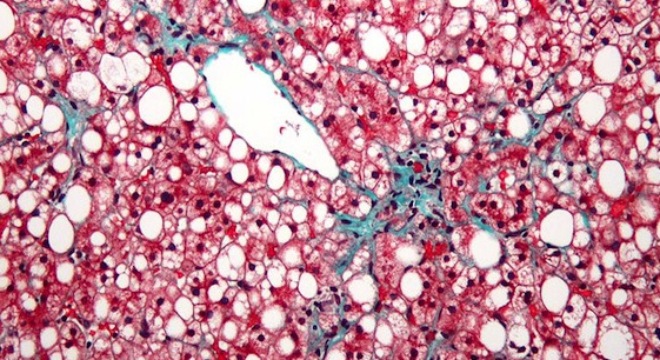

Ai cũng biết, ăn nhiều muối gây hại thận. Nhưng gan cũng phải chịu sự ảnh hưởng nặng nề không kém khi ăn nhiều muối.

Muối là một hợp chất hóa học gồm 2 nguyên tố Natri và Clo, 95% lượng muối đưa vào cơ thể đều qua gan và thận xử lý.

Lượng muối quá nhiều sẽ gây trở ngại cho quá trình đào thải các chất cặn bã dư thừa ra khỏi cơ thể, lâu ngày sẽ làm giảm khả năng hoạt động của gan và thận.

Cụ thể, nếu ăn quá 10 - 15g muối/ngày đối với người lớn và 3 - 5g muối/ngày đối với trẻ nhỏ là có thể tác động trực tiếp gây ảnh hưởng tới quá trình đào thải các chất cặn bã dư thừa và độc tố ra khỏi cơ thể, dần dần làm cho chức năng gan suy giảm.

Ăn quá nhiều muối cũng sẽ làm tăng huyết áp và dẫn đến bệnh gan nhiễm mỡ.